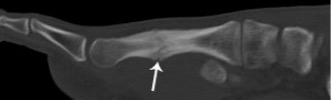

Stress fracture

- Occurs as a result of repetitive stresses or overload on bone

- Recognised sites include:

- tibia and fibula in long distance runners

- calcaneum and metatarsals secondary to walking (“March fracture”) and prolonged standing

- Seen as a linear band of sclerosis with periostitis

3rd metatarsal stress fracture with periostitis (arrowheads)